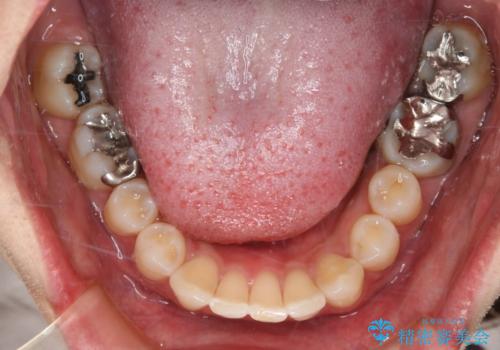

- 右上下6番の銀歯のやり変えを希望された患者様です。

切削量・形態を考慮し、上はセラミッククラウン、下はセラミックインレーでの治療を選択しました。

下はクラウンほど切削量が多くないと判断し、インレーでの治療を選択しました。